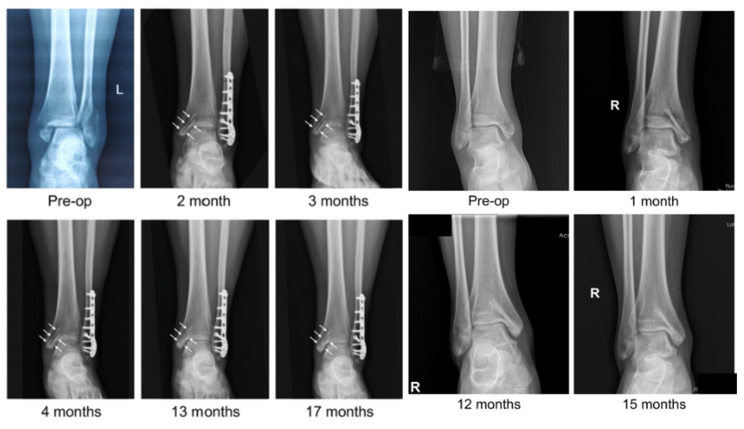

近日,国际骨科临床转化期刊《Journal of Orthopaedic Translation》在线发表了由上海交大戴尅戎院士、郝永强教授团队和丁文江院士、袁广银教授团队合作发表的可降解镁合金骨钉1-2年的临床试验观察结果,所有患者术后内踝骨折愈合,功能恢复。研究证实了可降解镁合金螺钉治疗内踝骨折的临床疗效及其生物安全性,为全降解镁合金植入物等高端医疗器械进一步的临床推广应用奠定了坚实基础,相关成果以“Effectiveness and safety of biodegradable Mg-Nd-Zn-Zr alloy screws for the treatment of medial malleolar fractures”为题在线发表于Journal of Orthopaedic Translation,27 (2021) 96–100。这是国内首个可降解医用镁合金临床试验的公开报道,也是国际首款含有功能涂层的可降解镁合金骨钉的临床试验结果的公开报道,具有里程碑意义。